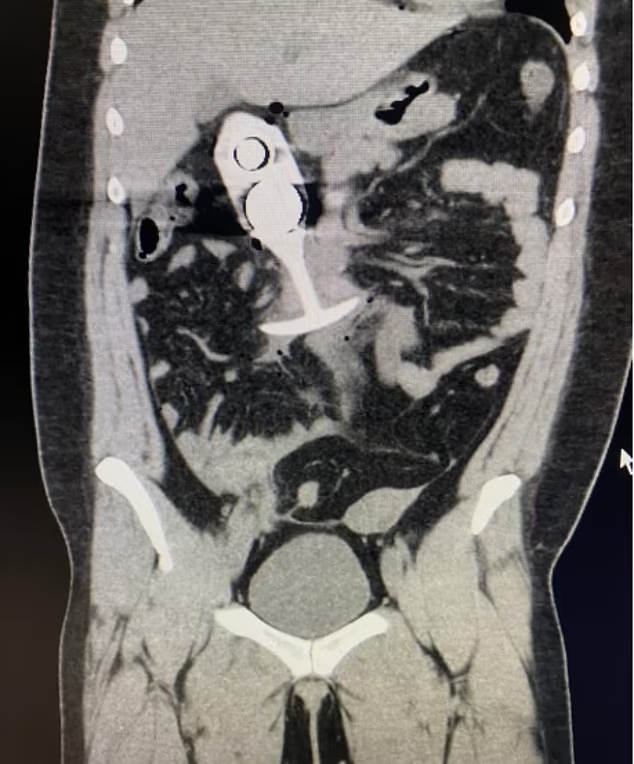

According to reports, the woman entered the scanner while wearing an adult toy she believed was made entirely of silicone. Although advertised as metal-free, the device concealed a metallic core. When the MRI’s powerful magnetic field activated, the metal was violently pulled upward inside her body, causing significant tissue and organ damage.

The woman’s scan image, shared widely on social media, has renewed discussion about MRI safety. Medical professionals stress that ignoring pre-procedure checklists can result in delayed diagnoses, repeated scans, or emergency surgery.